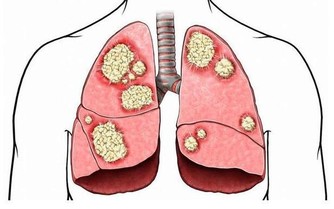

隨著年齡的增長,老年人各器官的生理功能逐漸衰退,許多疾病(特別是慢性病)的發生率上升,老人每天同時服用3-6種藥物不等,殊不知,即便是老年人常用的藥物,尤其是多種藥物聯用,也存在不小的潛在風險。今天就說一說其中10種常用且風險較高的藥物。

1.布洛芬:有肝腎損害風險,忌用量超標

老年人偶爾有個頭疼腦熱,在所難免。這時,布洛芬、雙氯芬酸鈉、對乙酰氨基酚等具有解熱、鎮痛功能的藥物是最常用的。尤其是布洛芬,在百姓心中,幾乎已成了解熱、鎮痛的代名詞。感冒、頭痛、牙疼,吃一片布洛芬,便萬事大吉。

實際上由於老年人體內代謝較慢,一般服用劑量應為正常劑量的一半,超量服用很有可能會導致肝臟和腎臟的損害。

另外,布洛芬還有消化道出血或潰瘍的不良反應,主要表現為噁心、嘔吐、胃痛、便血等。如果飯後再服用布洛芬,則能夠較好地規避此種風險。如果老年患者本身就有胃腸道疾病,則更應該引起注意。